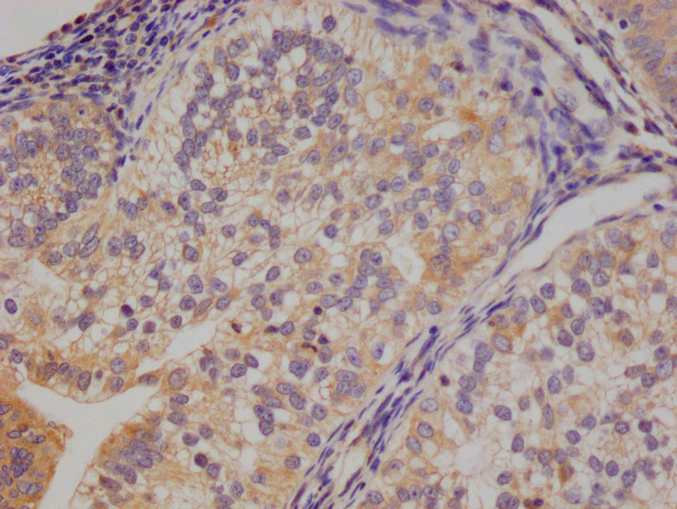

Immunohistochemistry of paraffin-embedded human colon cancer using CSB-PA010418PA10nphHU at dilution of 1:100